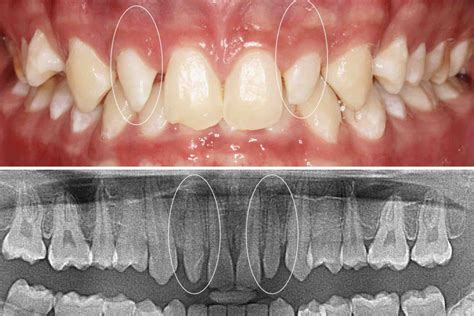

Los dientes conoides son una condición que puede afectar significativamente la estética de tu sonrisa. Estos dientes, ubicados justo detrás de los incisivos centrales, a menudo son más pequeños, puntiagudos o con forma cónica. Aproximadamente el 2-5% de la población presenta esta variación dental. En este artículo, exploraremos las opciones de tratamiento más efectivas, ayudándote a entender cuál podría ser la mejor elección para tu sonrisa.

Los incisivos cónicos son dientes que han experimentado un desarrollo anormal, resultando distinto en tamaño y forma. Esta condición puede afectar a uno o ambos incisivos laterales. Aunque su tamaño y forma pueden variar, típicamente son notablemente más pequeños que los incisivos laterales normales.

El impacto de los dientes cónicos va más allá de la estética. Estos dientes pueden afectar la mordida y la función masticatoria, aunque su principal preocupación suele ser la apariencia. Debido a su ubicación prominente en la sonrisa, los incisivos laterales conoides pueden hacer que los dientes parezcan desalineados o desproporcionados, afectando la confianza y la autoestima del individuo.

- La agenesia puntual o hipodoncia es la falta de 1 a 6 dientes. En estos casos, es muy habitual que el niño no realice el recambio dentario primario puesto que al no contar con el diente definitivo, el de leche no se cae. Esta anomalía está muy estrechamente relacionada con el conoidismo.